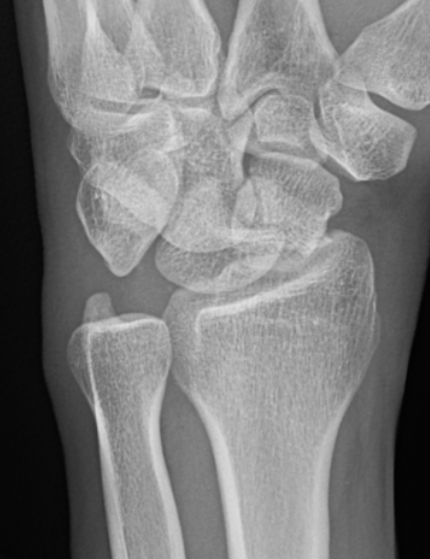

AP X-ray

Disruption of Gilula's 3 smooth carpal arcs / triangular lunate

Normal versus disruputed Gilula's carpal arcs

Piece of pie / triangular appearance of lunate